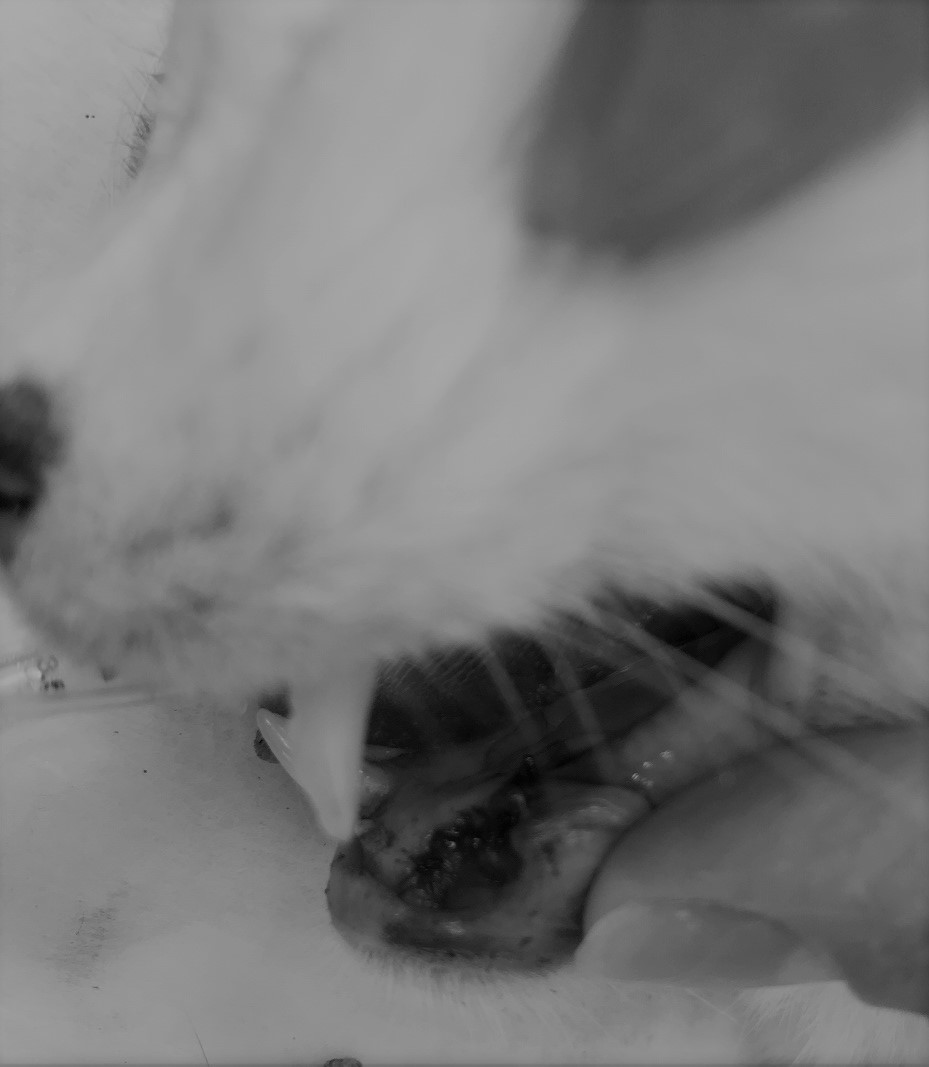

写真は口腔内検査当日のものです。左下アゴの腫れはなくなっており、皮膚が再生しています。

口の中に腫瘍はありませんでした。唾液腺の異常もみあたりません。